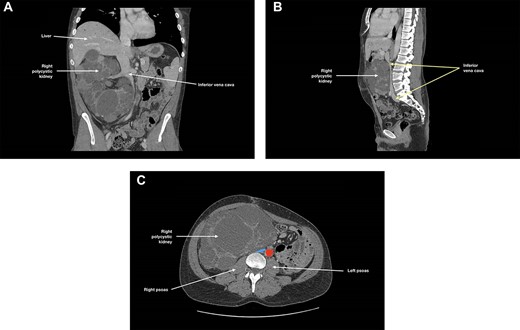

Ultrasound (US) and subsequent computed tomography (CT) of the abdomen and pelvis revealed compression of the left common iliac vein by a dominant cyst of the left polycystic kidney (Fig. 1), with extensive non-occlusive thrombus through to the left calf. There were also multiple hepatic cysts in both liver lobes, and the duodenal segments D1 and D2 had been displaced to the left, but there was no evidence to suggest bowel obstruction.

(A) Coronal, (B) sagittal and (C) axial views of the patient’s CT scan of his abdomen and pelvis at initial presentation; this showed enlarged polycystic kidneys, with the left kidney extending into the patient’s pelvis; there was compression of the left common iliac vein by a dominant cyst in the left polycystic kidney against the patient’s sacrum; in (c), the left common iliac vein is depicted in blue and the common iliac arteries are depicted in red; hepatic cysts and duodenal effacement are not visible in the selected planes; R, right; I, inferior; A, anterior; P, posterior.